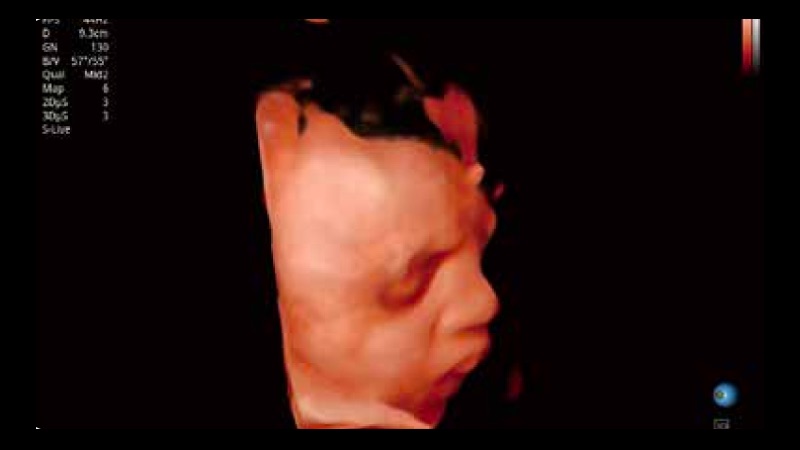

容积探头

凭借狗万官方网站先进的成像技术和优异的探头技术提供的清晰的图像表现,您可以更自信地做出临床决策。